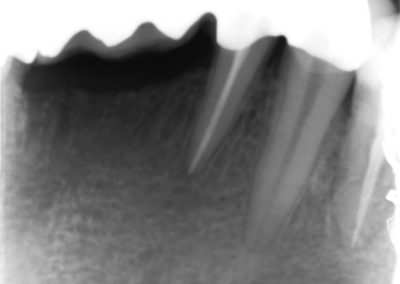

During the consultation, the dentist will first listen to your concerns and carry out appropriate tests to identify the right tooth that is causing pain. As a part of the diagnosis, your dentist will carry out various clinical tests to identify the right tooth and will take some radiographs which can aid in the diagnosis.

An access cavity is placed on the surface where the patient bites, to reach the root canals of the tooth. Once all the canals are identified, small files are used to remove the infected pulp.

Files of different sizes are used to eliminate bacteria and infection and to shape the canals. The canals are disinfected thoroughly with irrigants and later the canals will be sealed in 3 dimensions with a special medicament called gutta-percha to prevent reinfection of the tooth and the access cavity will be sealed with a temporary filling.